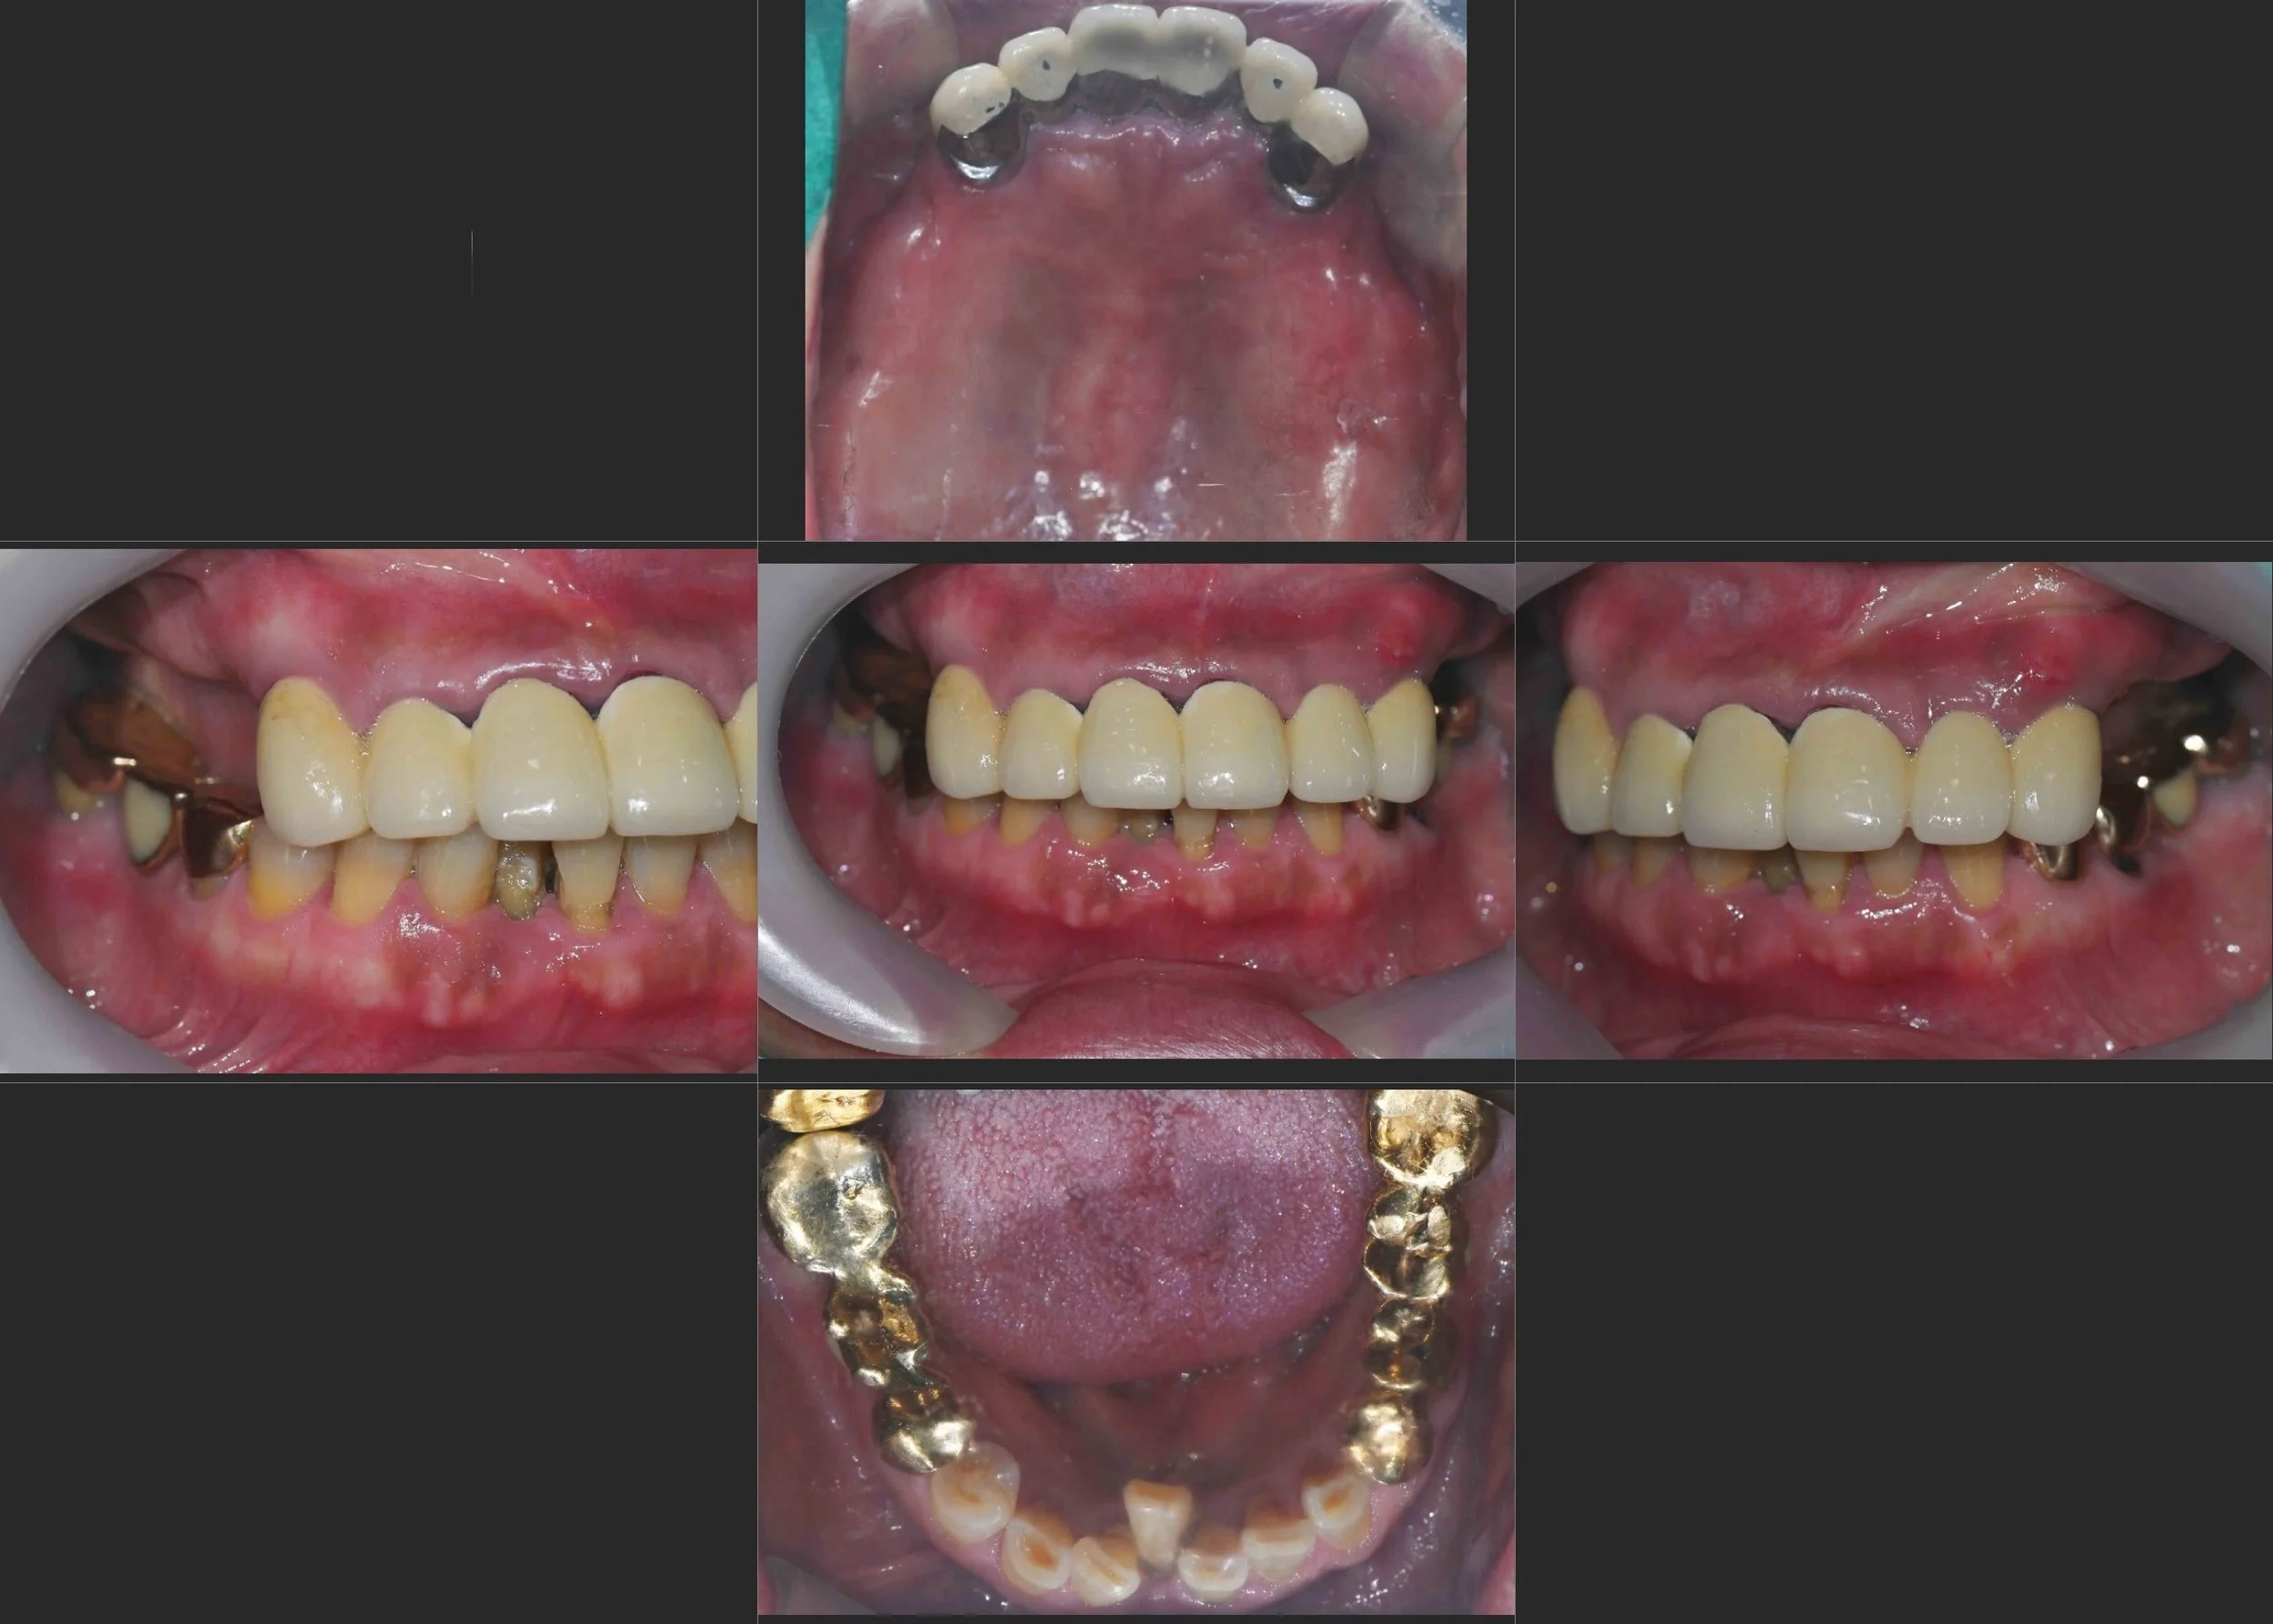

30. Strategic Full Mouth Rehabilitation: Balancing Clinical Goals and Financial Constraints

VDO Elevation and Aesthetic Reconstruction in a Male Patient in his 70s. A Cost-Effective Approach Restoring Functional Support up to the First Molars while Maximizing Natural Tooth Preservation.